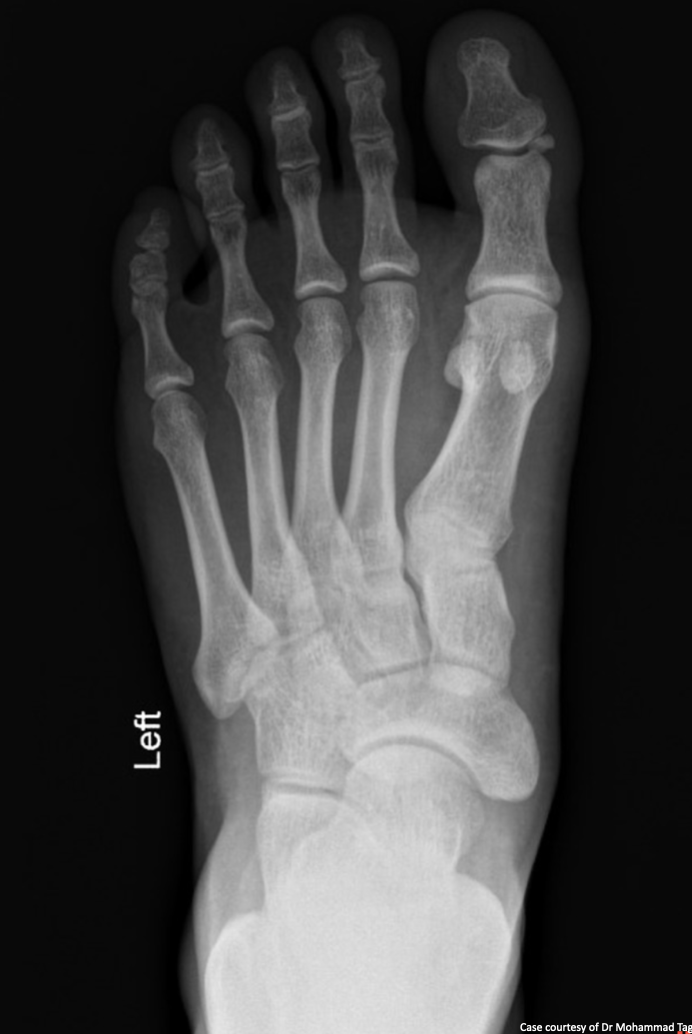

7

Q

What view is this?

A

DP